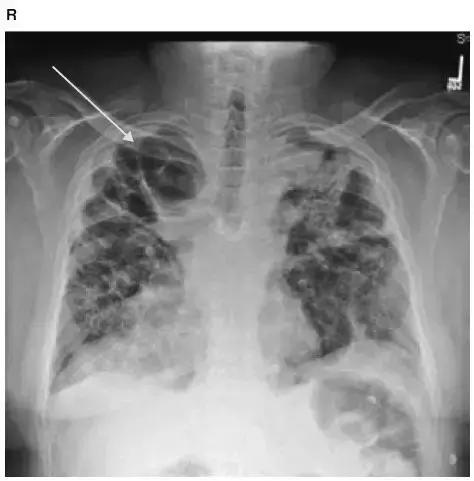

图4-26 Ⅳ期结节病胸片显示肺纤维化和空洞形成(白箭头)